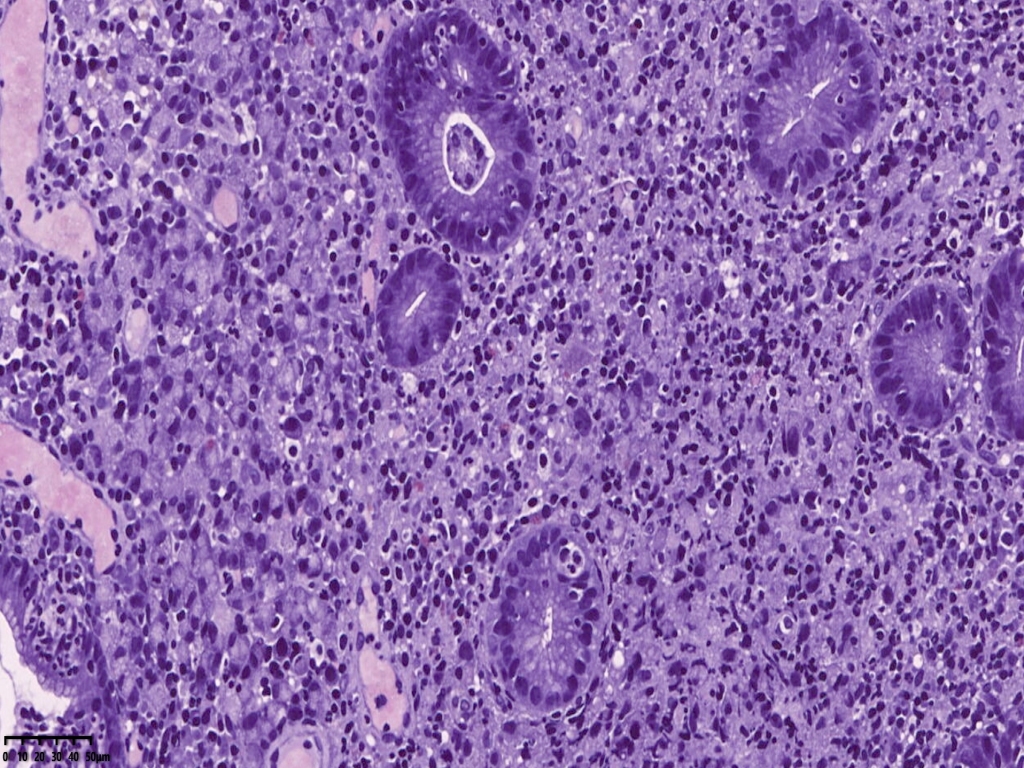

免疫组化标记后异型上皮细胞更显著。

CKpan

ck7